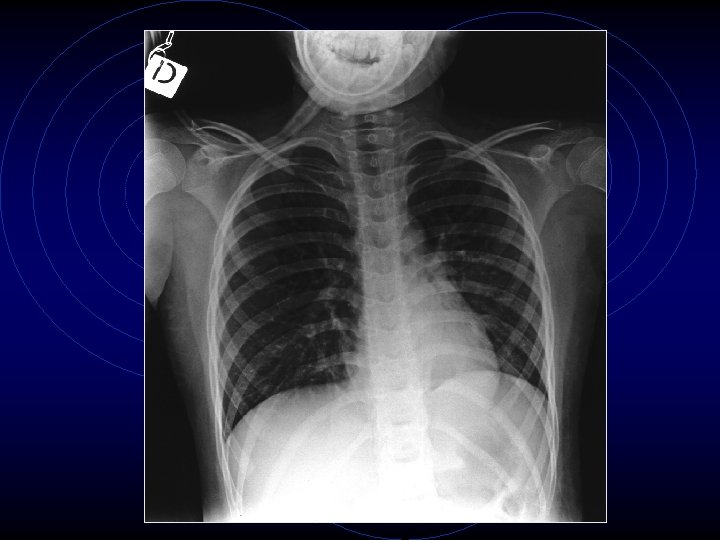

• Le indagini ematochimiche evidenziavano una modesta leucocitosi neutrofila (GB: 13340, N: 89, 3%) con PCR nei limiti della norma (< 0, 46 mg/dl) così come transaminasi, ionogramma, glicemia, azotemia, creatininemia, elettroforesi delle proteine • Veniva quindi eseguita radiografia del torace che dimostrava una modesta iperespansione dei campi polmonari bilateralmente con accentuazione del disegno polmonare

• Il caso presenta un peculiare interesse per il rapporto tra Mycoplasma e asma. In questo caso la difficoltà diagnostica sulla possibile etiologia da Mycoplasma era legata al fatto che era preesistente una patologia asmatica e soprattutto perché il quadro radiologico era poco significativo, anche se la patologia da Mycoplasma tende a presentarsi con quadri radiologici polimorfi.